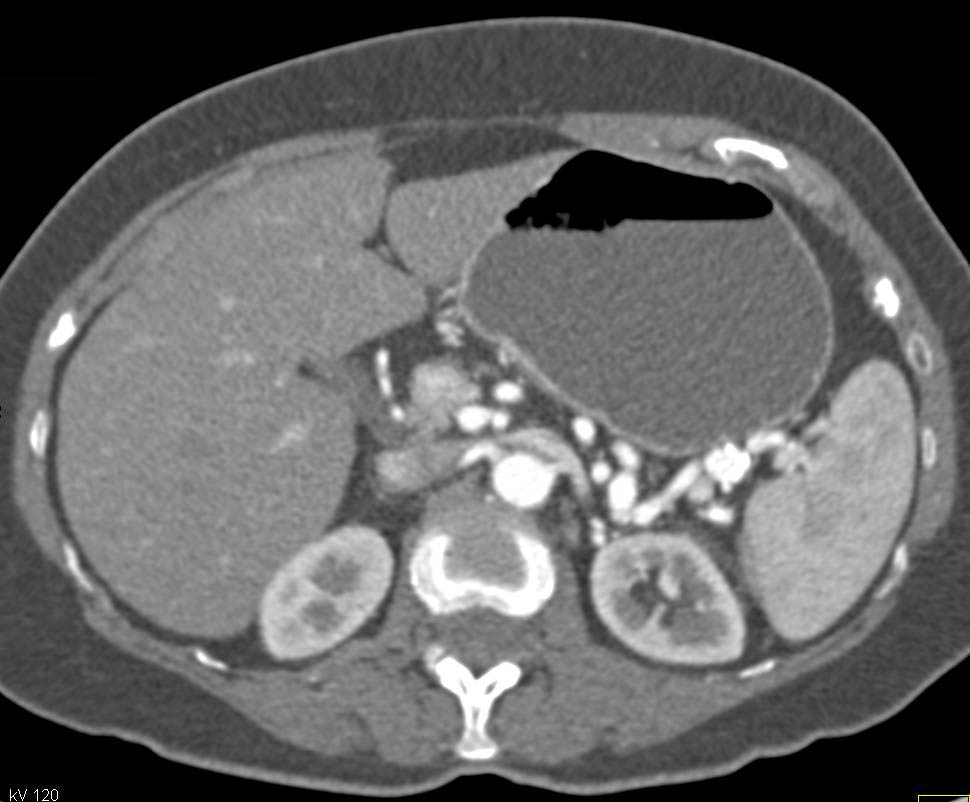

Endovascular Stent withFlow Also Through a Fem-Fem Bypass Graft